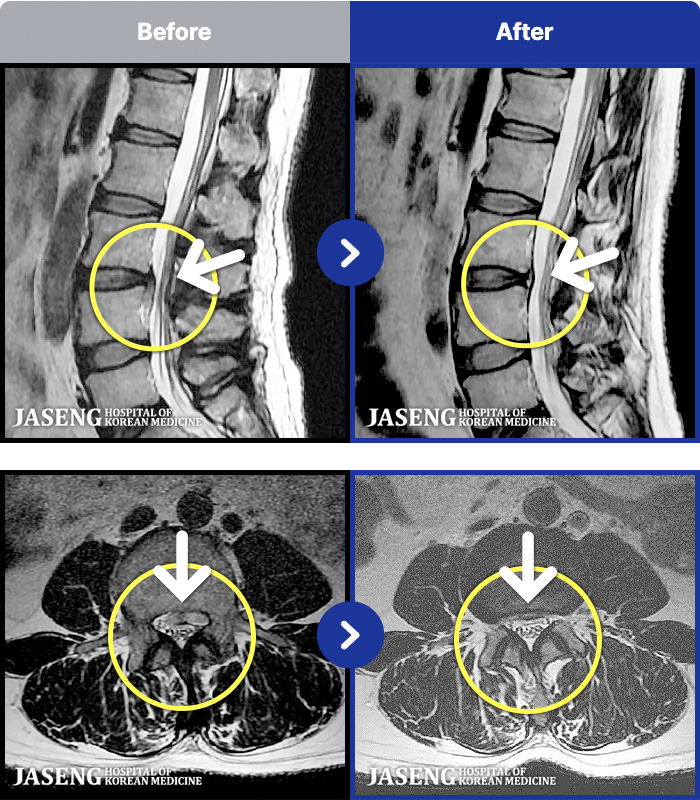

- MRI ġ

MRI ġ

1,301 MRI ũ ʸ Ȯϼ.